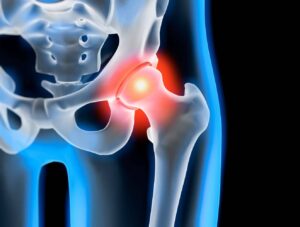

Die Orthopädie ist ein medizinisches Fachgebiet, das sich mit der Prävention, Diagnose und Behandlung von Erkrankungen und Verletzungen des Bewegungsapparates beschäftigt. Knochen, Gelenke, Muskeln, Sehnen und Bänder müssen gemeinsam funktionieren, um uns Beweglichkeit und Stabilität zu ermöglichen.

Auf unserer Seite finden Sie umfangreiche Informationen zu orthopädischen Beschwerden und Erkrankungen. Von der Arthrose über Bandscheibenvorfälle bis hin zu Kreuzbandriss und weiteren Sportverletzungen: wir geben Ihnen einen Überblick über die häufigsten orthopädischen Krankheitsbilder, wie sie behandelt werden können und inwieweit ein Bildgebungsverfahren, wie eine (z.B. MRT Knie, Rücken MRT) bei der Diagnose bei der Diagnose unterstützend wirken können.